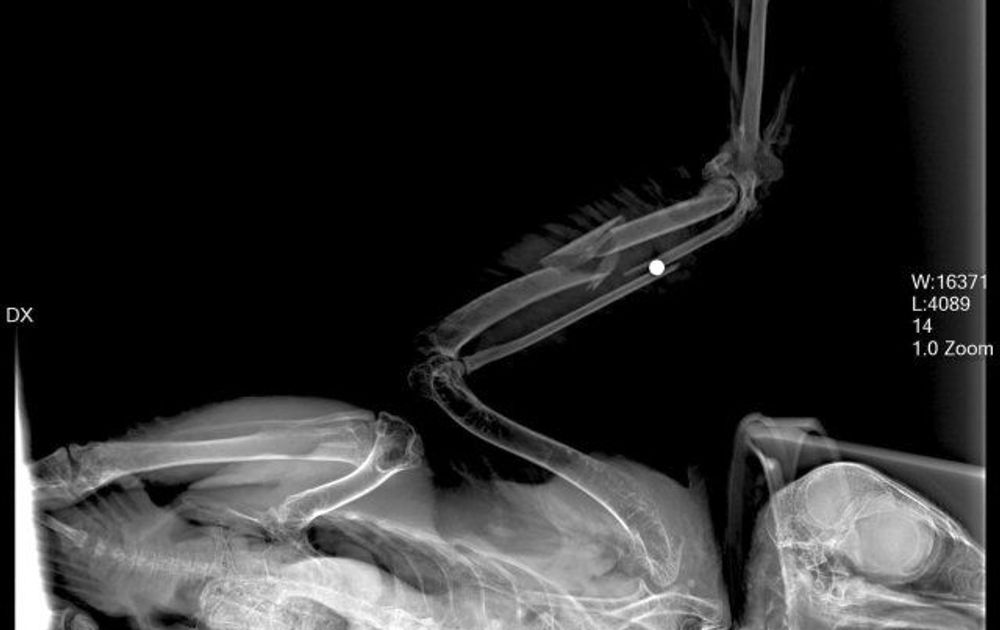

Het was woensdag 27 juli 2011. Bij velen komt de liefde voor de slechtvalk in het algemeen, en voor S2 in het bijzonder, direct naar boven. S2 werd in goede conditie gevonden, maar met een ernstige verwonding aan haar vleugel in Gemert. Er werd onmiddellijk contact gezocht met een deskundige dierenarts. Uit röntgenfoto's bleek dat haar vleugel op meerdere plaatsen gebroken was. Maar wat zien we nog meer op de foto? Een hagelkorrel! Onze S2 was neergeschoten met een jachtgeweer! Er werd destijds aangifte gedaan, want het doden van roofvogels is een strafbaar feit. Helaas is de dader (laat ik die term maar gebruiken, want andere woorden zijn niet passend) nooit gepakt.

Een vogel met een schotwond en meerdere breuken, dat klinkt als het einde en is dat ook altijd het geval in vergelijkbare situaties. Maar nu niet, hoor. Een operatie was mogelijk, al was de kans op succes klein. Dierenartsen Carolien Hommers en Dirk Riemersma voerde een ingewikkelde operatie uit die drie uur duurde. De kogel werd verwijderd en de vleugel extern gefixeerd met pennen, die vier tot zes weken moesten blijven zitten. Na de succesvolle operatie kwam S2 bij uit de narcose, maar dan ging het weer (bijna) mis. S2 stopte plots met ademen! Dankzij een alerte assistente kreeg S2 mond-op-snavelbeademing (en dit is geen grap) en een hartmassage van dierenarts Caroline, S2 kwam gelukkig weer bij en de operatie was alsnog geslaagd.

S2. Direct na de operatie!